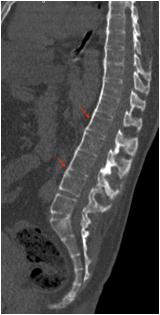

Radiological imaging was done in all the cases. USG findings revealed solitary masses in 45 cases (80.35%) and diffuse masses in 11 (19.64%). Solitary masses were around 45 in number out of which 30 were diagnosed as HCC. Right lobe had around 30 (66.7%) whereas left lobe had 15 (33.33%) masses respectively. Maximum (SOL’s) observed showed hyper-echogenicity present in 43 cases (76.78%). Heterogenous echotexture was observed in 6 cases (10.71%) (Fig 1).

CT scan was done in two patients which showed multiple well defined hyperdense lesions and hypodense lesions in another patient. Cyto-radiological correlation of hepatic masses was seen in 94% cases (Fig 2).

Fig 1 — USG liver showing well defined heteroechoic lesion in left lobe

Fig 2 — CT liver showing multiple enhancing focal hepatic lesions suggestive of metastasis